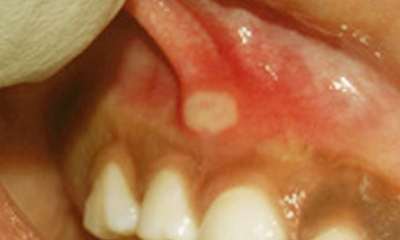

Стоматит на десне

Иногда, перед тем как понять как выглядит стоматит его можно спутать с иным заболеванием. Стоматит на десне (фото 6) может начаться маленьким твердым зернышком, совсем как симптом корневого воспаления зуба. Только когда краснеют десневые сосочки и краевые участки вокруг зубов, появляется зуд, налет, можно догадаться, что это стоматит на десне.